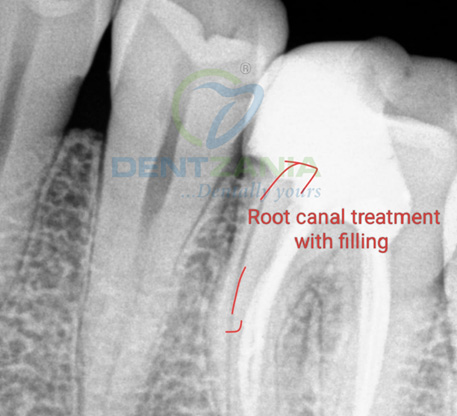

1. Diagnosis & X-Ray

X-rays are taken to assess the damage

The infected pulp is removed and the tooth is filled with root filling

If the nerve of a tooth has become decayed or infected, a Root Canal may save the tooth itself whilst removing the problematic root. The nerve part of the tooth, along with the pulp (living tissue inside the tooth) and any bacteria or decay present is removed; then the tooth is sealed with special root-filling cement all the way to the tip of the root. This will save your tooth once the root is filled and sealed properly to the very apex; and it gets rid of the painful soft tissue and leaves a hard shell. A dental crown is then fitted to ensure the tooth has full functionality within your mouth.